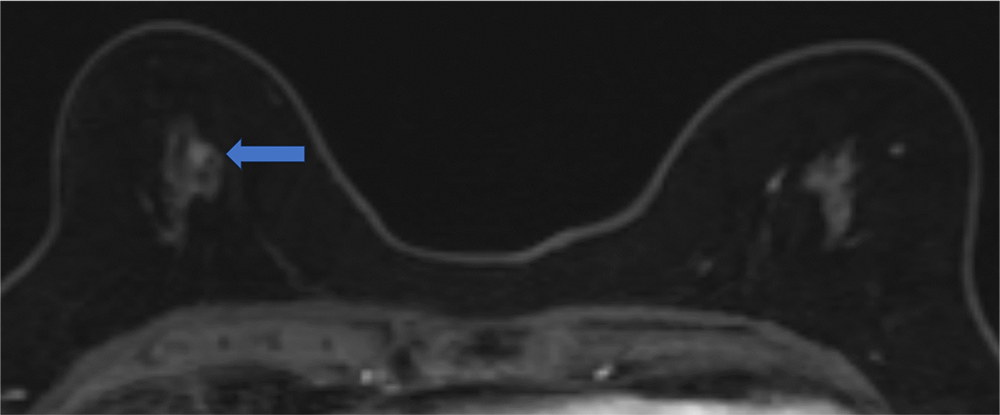

6. 造影後高分解能画像

病変は扁平な形状で内部にはdark internal septation様の構造が見られる。